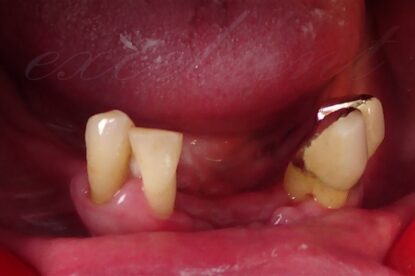

Η συγκεκριμένη ασθενής είχε κατά το παρελθόν κατασκευάσει πλήθος οδοντοστοιχιών(μασέλες), τις οποίες απέρριπτε καθώς είχαν ελλιπή συγκράτηση και της δημιουργούσαν αντανακλαστικό εμέτου.

Με τις νέες ακίνητες αποκαταστάσεις επανήλθε τόσο η αυτοπεποίθηση και η άνεση της ασθενούς όσο και η μασητική της ικανότητα στα προ της απώλειας των δοντιών της επίπεδα.